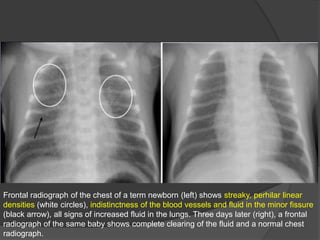

TRANSIENT TACHYPNEA OF THE NEWBORN

(Wet lung disease)

Definitions

• Transient tachypnea occurs when liquid in the fetal lung is removed slowly or

incompletely from newborn lung and there is increased absorption by lymphatics

and capillaries

o Lack of normal thoracic compression that normally occurs during vaginal delivery and

is bipassed via C-sections

o Lack of normal breathing may occur with sedated infants

Best diagnostic clue: Prominent interstitial pattern in lung with history of C-section.

The lungs usually are affected diffusely and symmetrically, and the condition is

commonly accompanied by a small pleural effusion.

Chest radiographs

• Findings similar to pulmonary edema

• Prominent intersitial markings with normal heart size

• Diffuse, bilateral and somewhat symmetric increase in lung markings

• Pleural effusions may be present

• Fluid in the fissures

• Normal to hyperinflated lung volumes

• Interstitial pattern and other findings resolve and is normal within 72 hours. Clearing

continues from peripheral to central and from upper to lower lung.

•The radiographic appearance can mimic the diffuse granular appearance of hyaline

membrane disease but without the pulmonary underaeration.

Frontal radiograph of the chest of a term newborn (left) shows streaky, perhilar linear

densities (white circles), indistinctness of the blood vessels and fluid in the minor fissure

(black arrow), all signs of increased fluid in the lungs. Three days later (right), a frontal

radiograph of the same baby shows complete clearing of the fluid and a normal chest

radiograph.